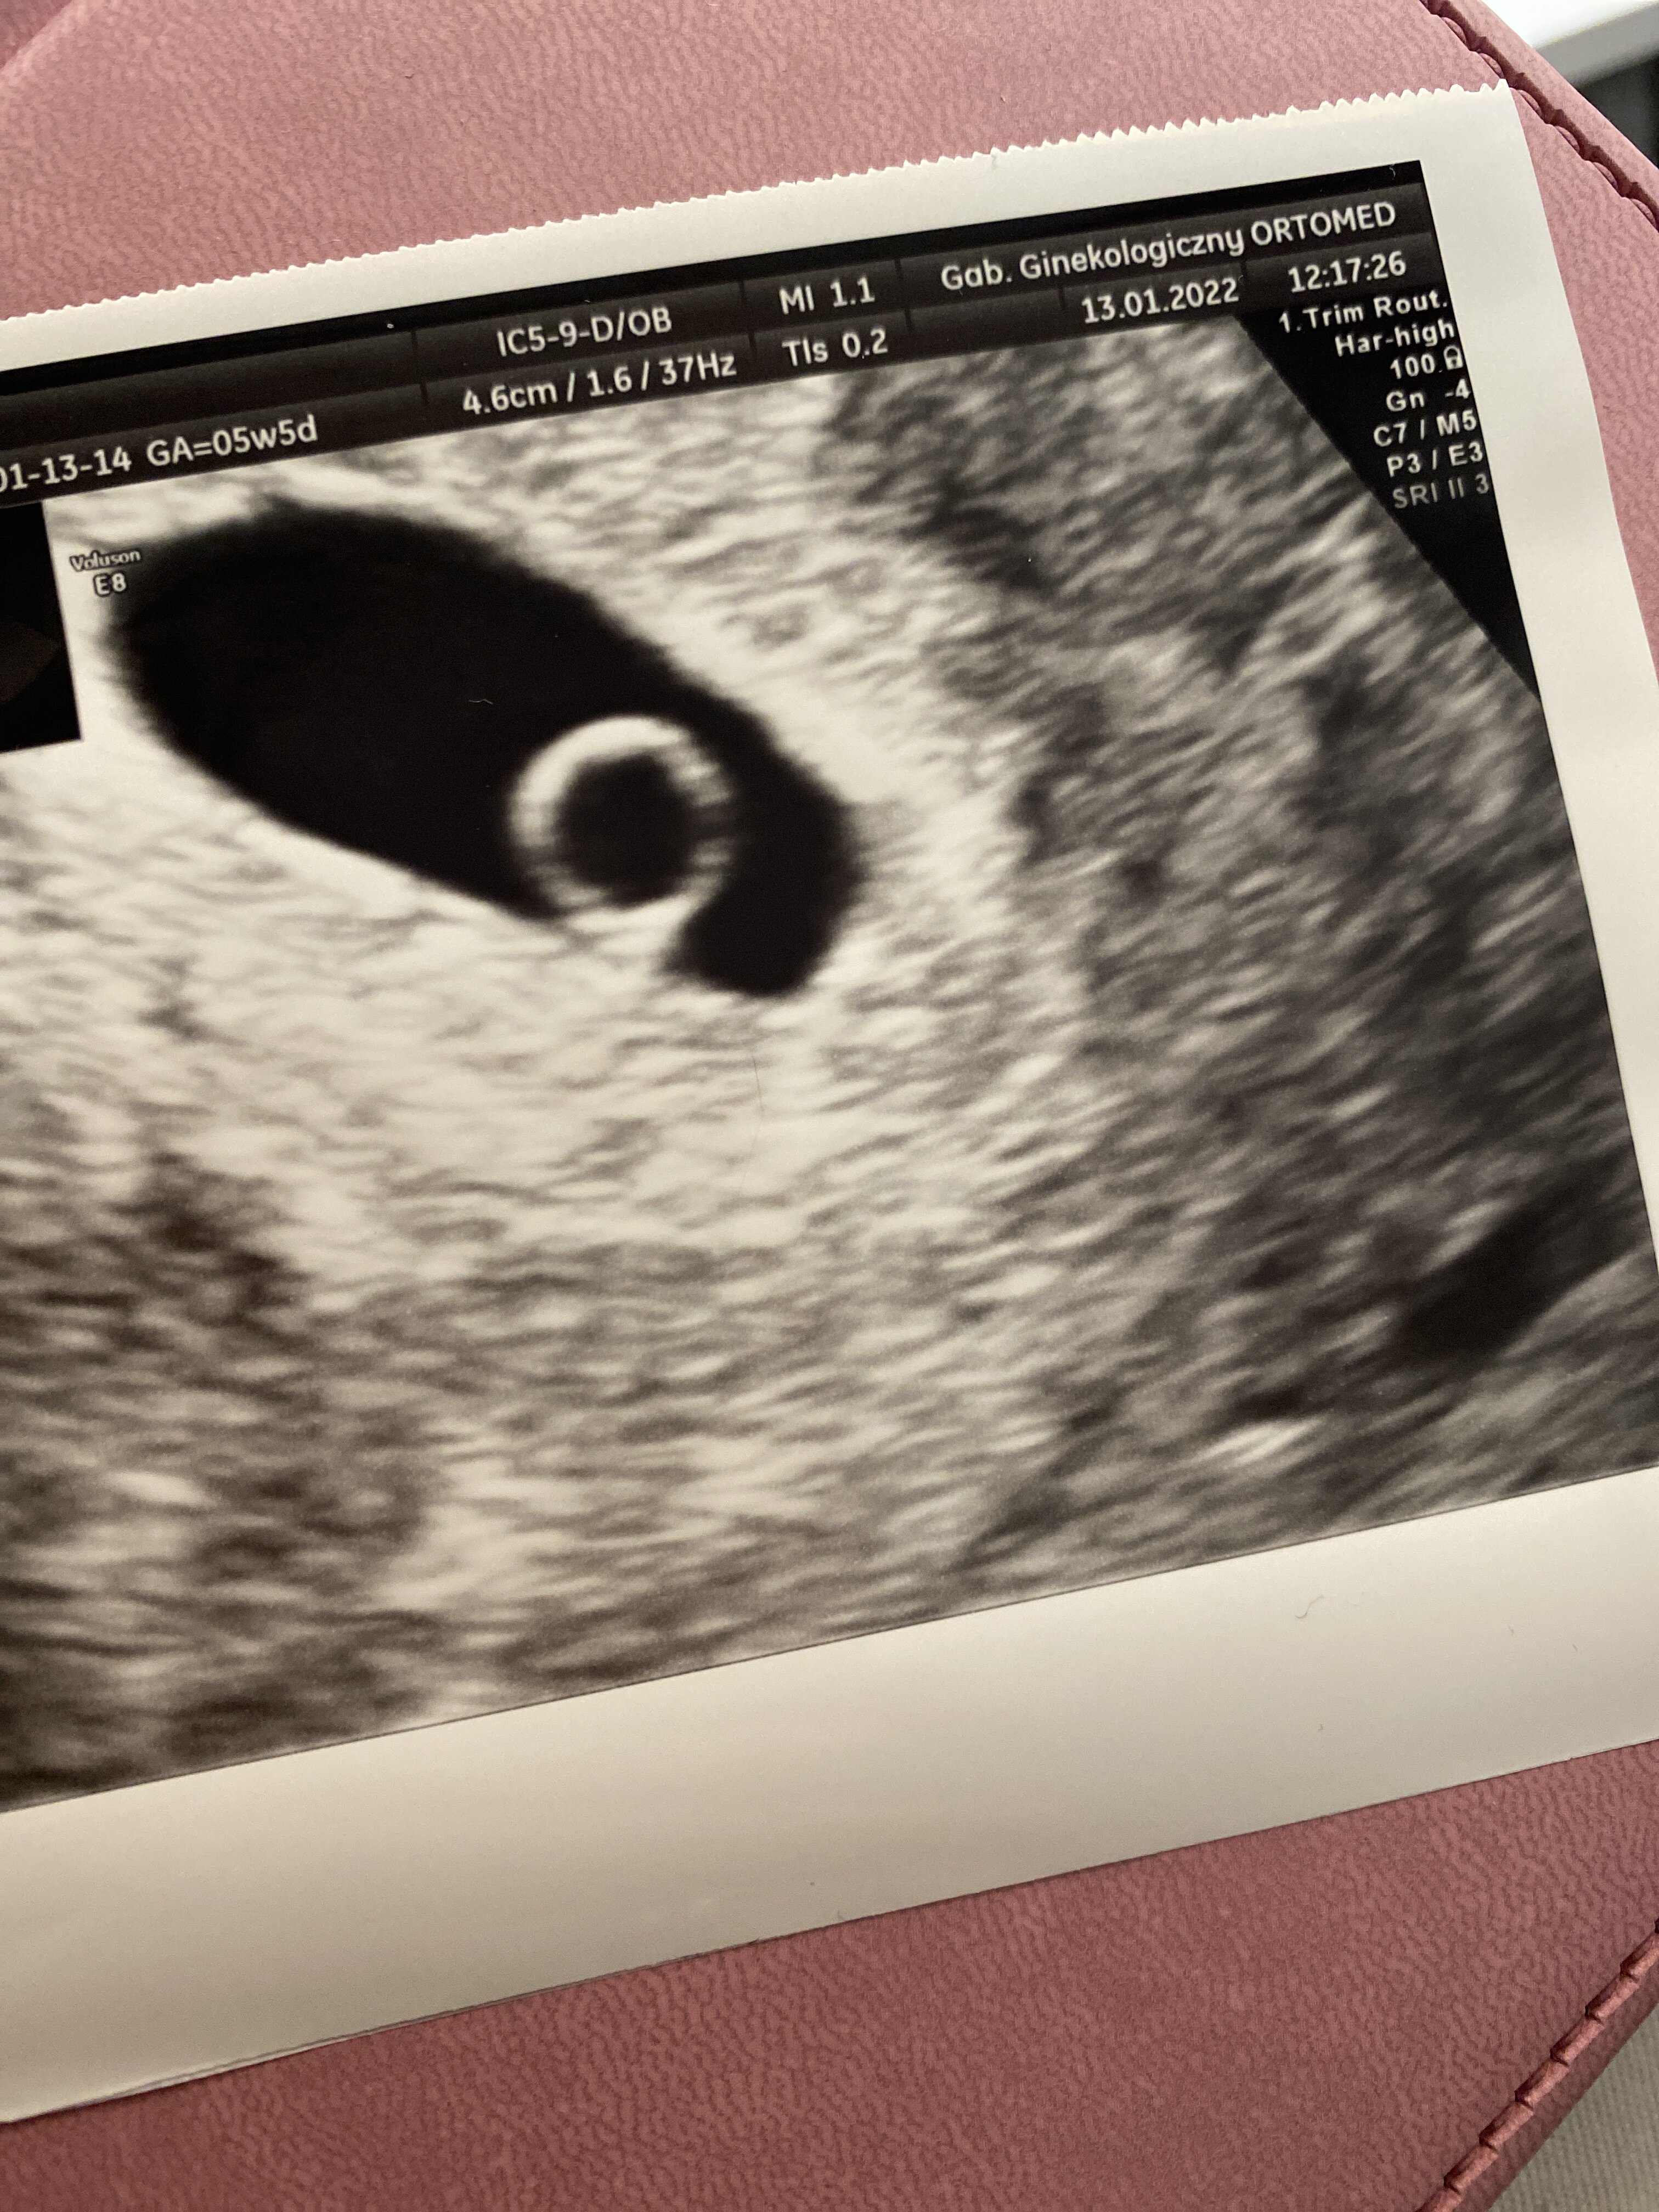

Ja byłam 5+5 i było widac maluteńki zarodek , 3 lutego wizyta już mam nadzieje ze usłyszęDziewczyny, kiedy macie pierwsze USG i który to będzie u Was tydzien ciąży? Ja jutro po wynikach bety będę dzwonić i się umawiać. Nie chce pójść za wcześnie, żeby się nie stresować czemu nie ma jeszcze zarodka albo serduszka...